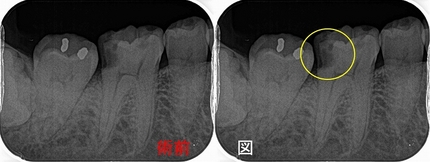

レントゲン

2026 EEdental NNS (1).jpg

口腔内写真

2026 EEdental NNS (2).jpg

低目にレジンが詰めてあります。

患者さんには咬頭が無くなっており、中で虫歯もひろがっていそうだから

メタルアンレーで治しましょうと説明

治療を開始すると、「え!?」というぐらい詰め物が深い

歯茎の中のレジンも途中までしか詰めれておらず隙間から歯の中に歯茎が入り込んで来ている・・・

途中からこれ初発は虫歯ではなく歯冠破折で、長い期間で隙間から2次カリエスが出来たケースだと分かってきました。

歯の中の歯茎は電メスを使い除去

虫歯を削り終わると

2026 EEdental NNS (3).jpg

露髄した部分には第3象牙質が見られます。

エナメル質をなるべく残す為にEENOスフィアなどを使いくり抜くように虫歯を削っています。

ただ、こうなるとメタル修復するよりレジンで治した方が良いと判断し

患者さんとお母さんに理由を説明してレジン充填を行いました。

術前⇒術後

2026 EEdental NNS (5).jpg

2026 EEdental NNS (4).jpg

最後に咬合をチェックすると臼歯部に側方運動時のガイドがあり、

たぶん、昔もこのガイドが極端に強くて割れたんだろうなと推測。

2026 EEdental NNS (6).jpg

*最初の図と同じ割れ方になってました。

遠心にも似たようなガイドがあったので、最後に側方運動の咬合調整を行い終了となりました。

若い患者さんでも、夜間の歯ぎしりが大きい人はこのように歯冠破折を起こすことがあります。